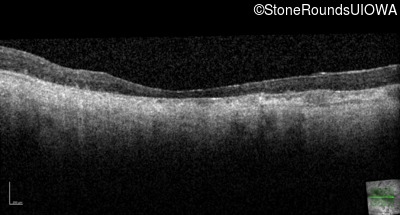

Age at visit: 61 years